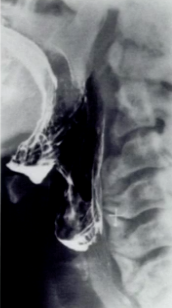

What causes barium to stop on the left side of the image?

Epiglottis